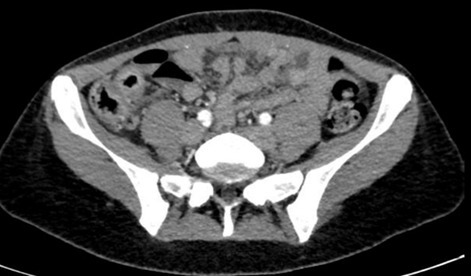

– une colite aiguë grave pouvant être inaugurale d’une maladie inflammatoire chronique de l’intestin (MICI). Ici, c’est un diagnostic possible car la patiente décrit des troubles digestifs évoluant depuis plusieurs années et elle fume, ce qui est un facteur de risque de développer une maladie de Crohn. Les critères de Truelove et Witts définissent la colite aiguë grave : > 6 selles sanglantes/24 h + protéine C réactive (CRP) > 30 mg/L ou hémoglobine < 10,5 g/dL ou température > 37,8 °C OU fréquence cardiaque > 90 bpm.